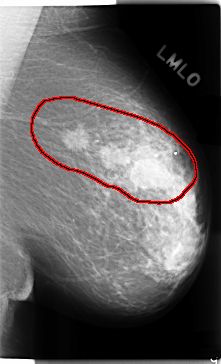

C_0112_1.LEFT_MLO

LEFT_MLO LINES 4720 PIXELS_PER_LINE 2872 BITS_PER_PIXEL 12 RESOLUTION 50 OVERLAY

FILE: C_0112_1.LEFT_MLO.OVERLAY

TOTAL_ABNORMALITIES 1

ABNORMALITY 1

LESION_TYPE MASS SHAPE IRREGULAR MARGINS SPICULATED

ASSESSMENT 5

SUBTLETY 5

PATHOLOGY MALIGNANT

TOTAL_OUTLINES 1

BOUNDARY